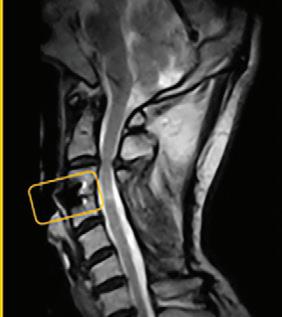

What a weight-bearing MRI reveals vs. a Supine MRI

G-scan Brio Reveals What Supine MRI Misses

Conventional MRI may not demonstrate the pathology related to these symptoms, but G-scan Brio gives you a new point of view so you can accurately diagnose MSK pathologies affected by weight-bearing position.

The G-scan Bro is superior to other MRIs because both the magnet and patient can rotate from 0 to 90 degrees.

G-scan Brio offers a revolutionary MRI approach that increases diagnostic accuracy and confidence for musculoskeletal applications.

G-Scan - Anterolistesis G-Scan - Disc Modification Cervical scan

Supine MRI G-Scan - Anterolistesis G-Scan - Disc Modification Cervical scan More Detail, Better Accuracy,